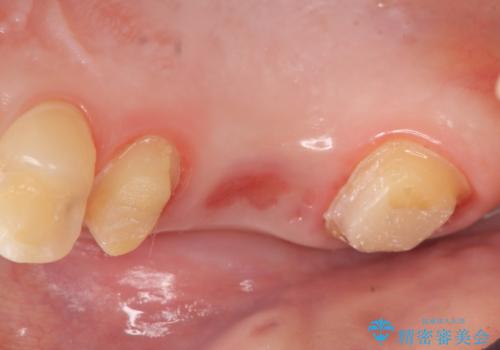

- 右上の奥歯が欠けてしまったので診て欲しいといらっしゃった方の症例です。

右上6番目の歯は虫歯が深く、保存が難しかったため抜歯しました。